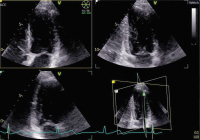

Echo

Abbildung 5: AS ohne KM: kein CW-Spektrum bei sehr schlechten Schallbedingungen

Keywords: EchoKardiologie

Abbildung 6: AS mit KM: gutes CW-Spektrum; gleicher Patient wie Abb. 5.